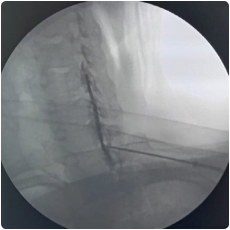

Intraop fluoroscopy image of needle placement at the cervical facet

Intraop image of cervical epidural injection